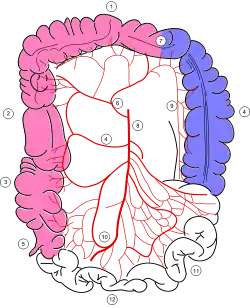

Frontal view of the abdominal aorta and the territory supplied by the inferior mesenteric artery. The arteries on the right side (left side of image) arise from the superior mesenteric artery (SMA). The marginal artery (not labeled) connects the middle colic artery (a branch of the SMA) to the left colic artery (a branch of the IMA). | |

Colonic blood supply (Marginal artery is #9) | |